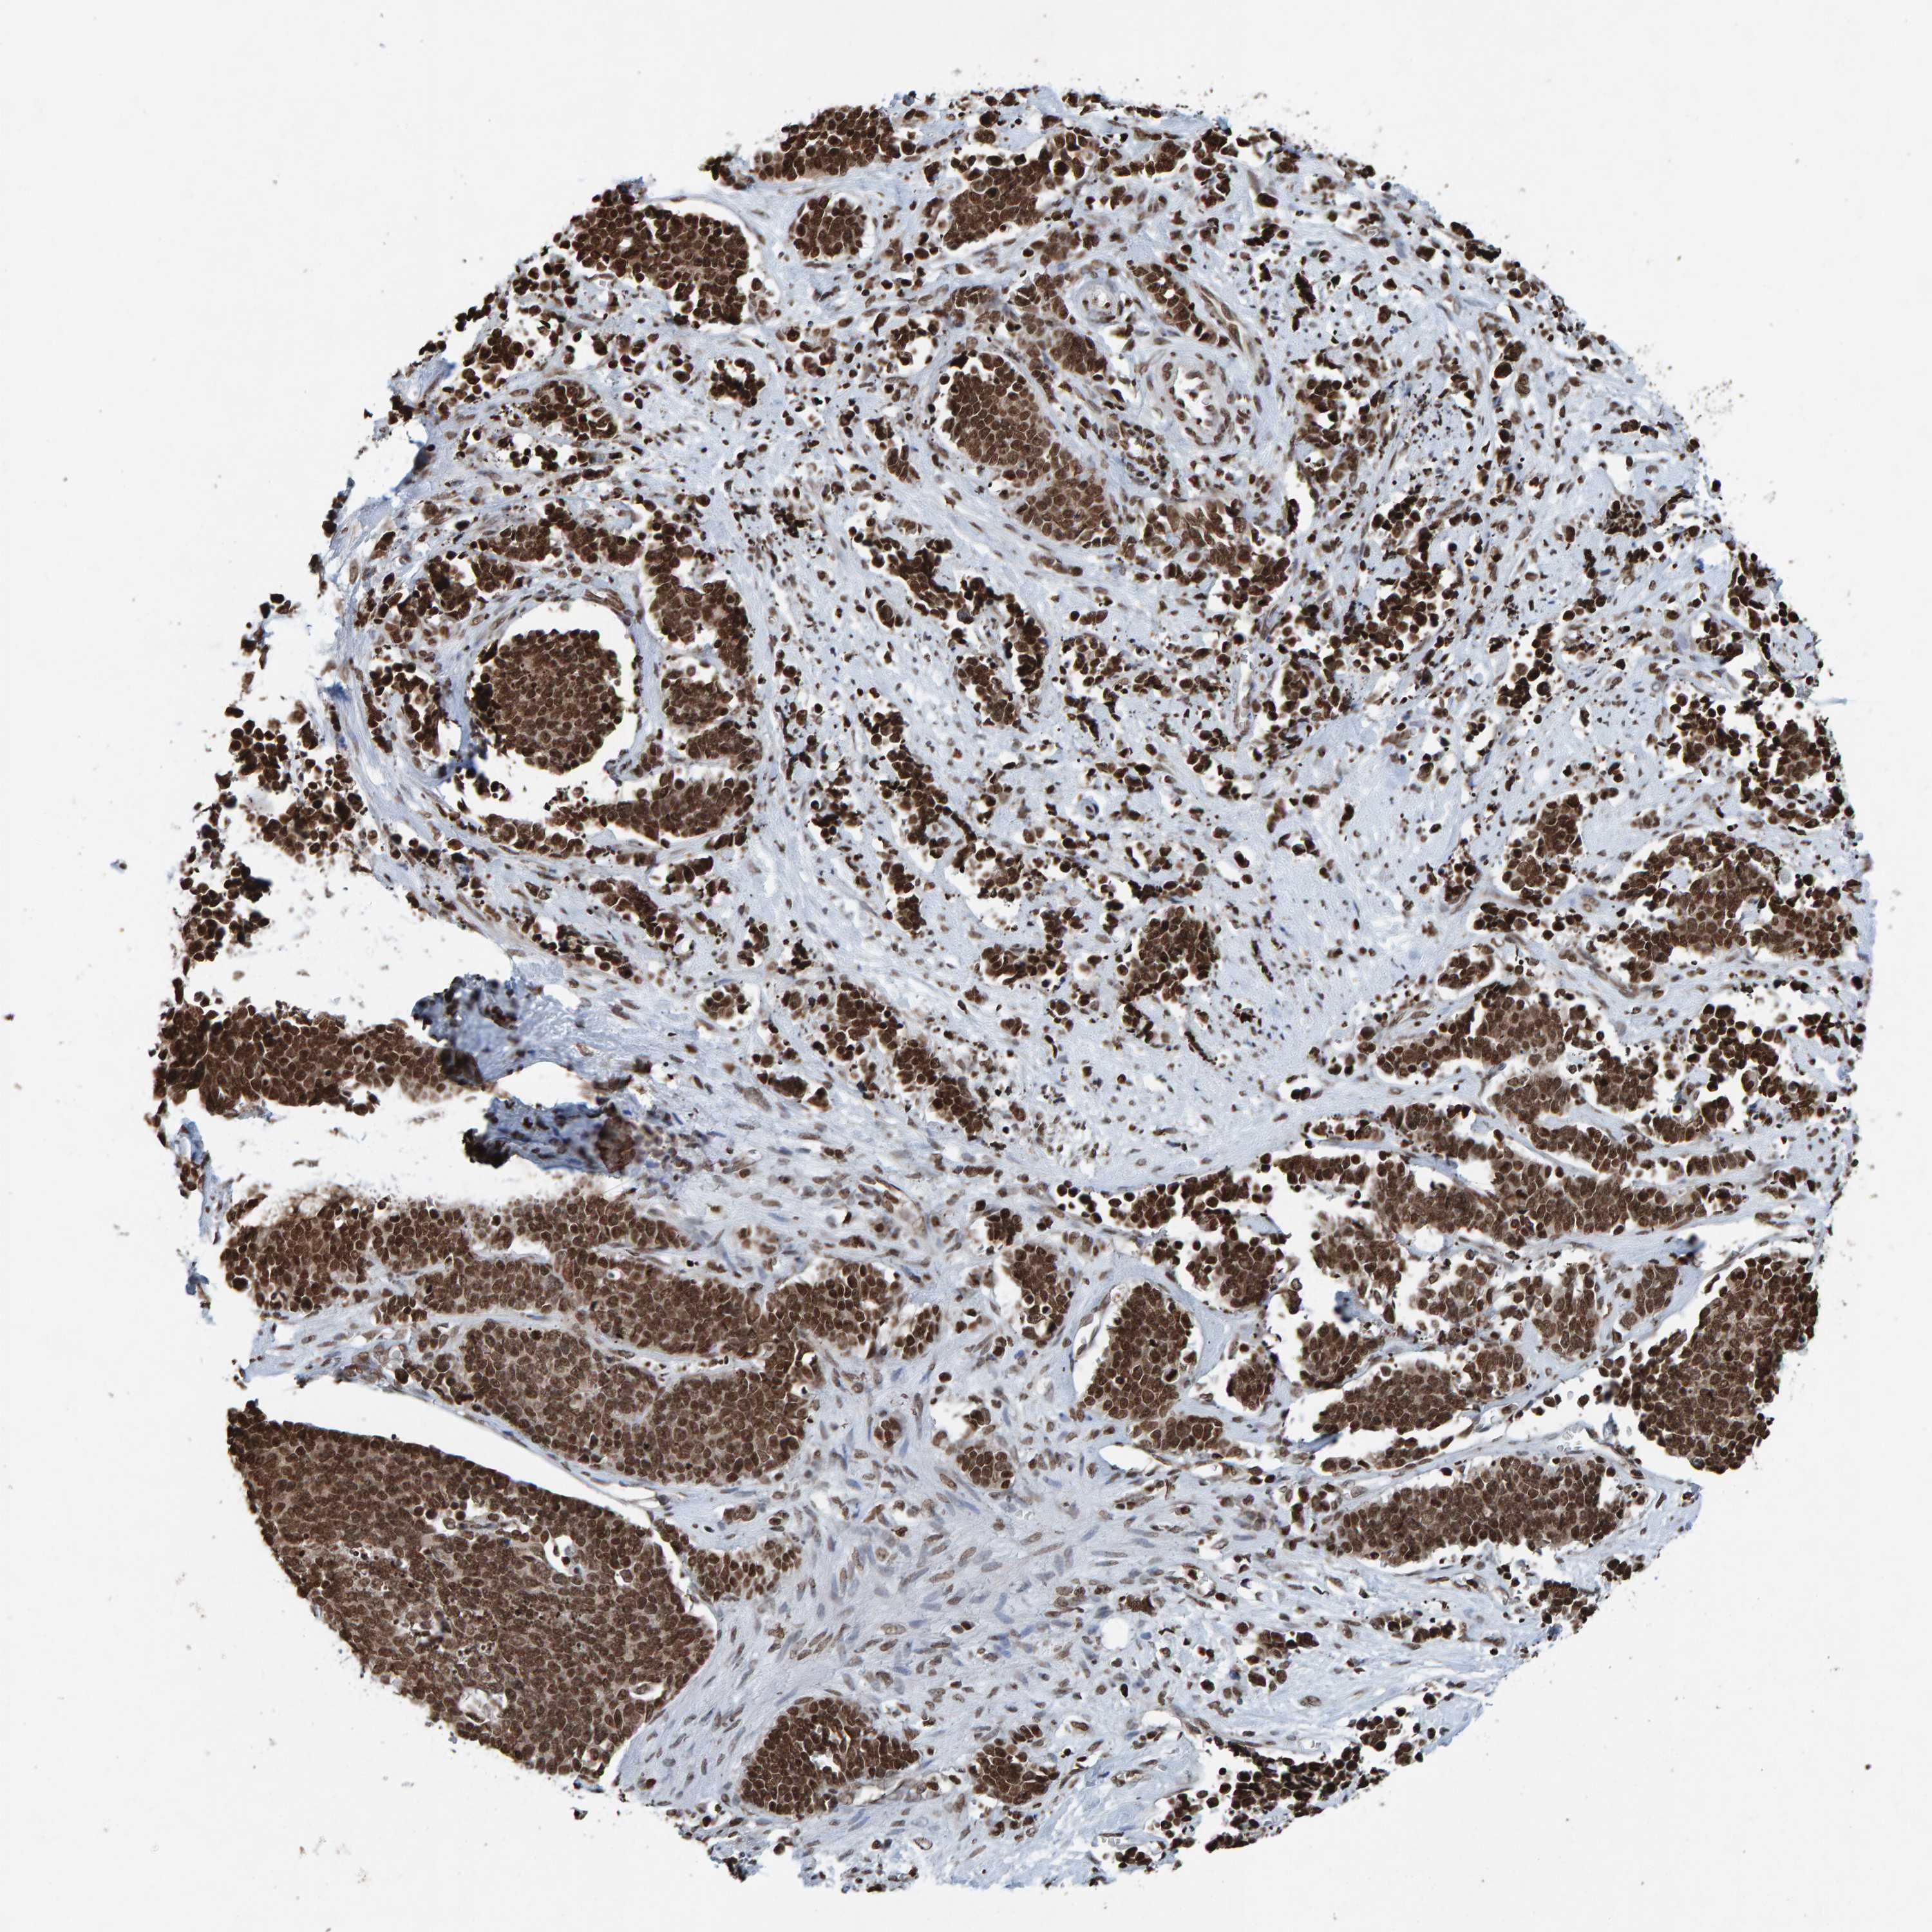

CERVICAL CANCER - Protein expressioni

A mouse-over function shows sample information and annotation data. Click on an image to view it in a full screen mode. Samples can be filtered based on level of antibody staining by selecting one or several of the following categories: high, medium, low and not detected. The assay and annotation is described here.

Note that samples used for immunohistochemistry by the Human Protein Atlas do not correspond to samples in the TCGA dataset.

Antibody stainingi

Antibody staining in the annotated cell types in the current human tissue is reported as not detected, low, medium, or high, based on conventional immunohistochemistry profiling in selected tissues. This score is based on the combination of the staining intensity and fraction of stained cells.

Each image is clickable and will lead to virtual microscopy that enables deeper exploration of all samples and also displays staining intensity scores, fraction scores and subcellular localization as well as patient and tissue information for each sample.

Antibody HPA057236

Antibody CAB022549

Staining

High

Medium

Low

Not detected

Intensity

Strong

Moderate

Weak

Negative

Quantity

>75%

75%-25%

<25%

None

Location

Nuclear

Cytoplasmic/membranous

Cytoplasmic/membranous,nuclear

Squamous cell carcinoma, NOS

Adenocarcinoma, NOS